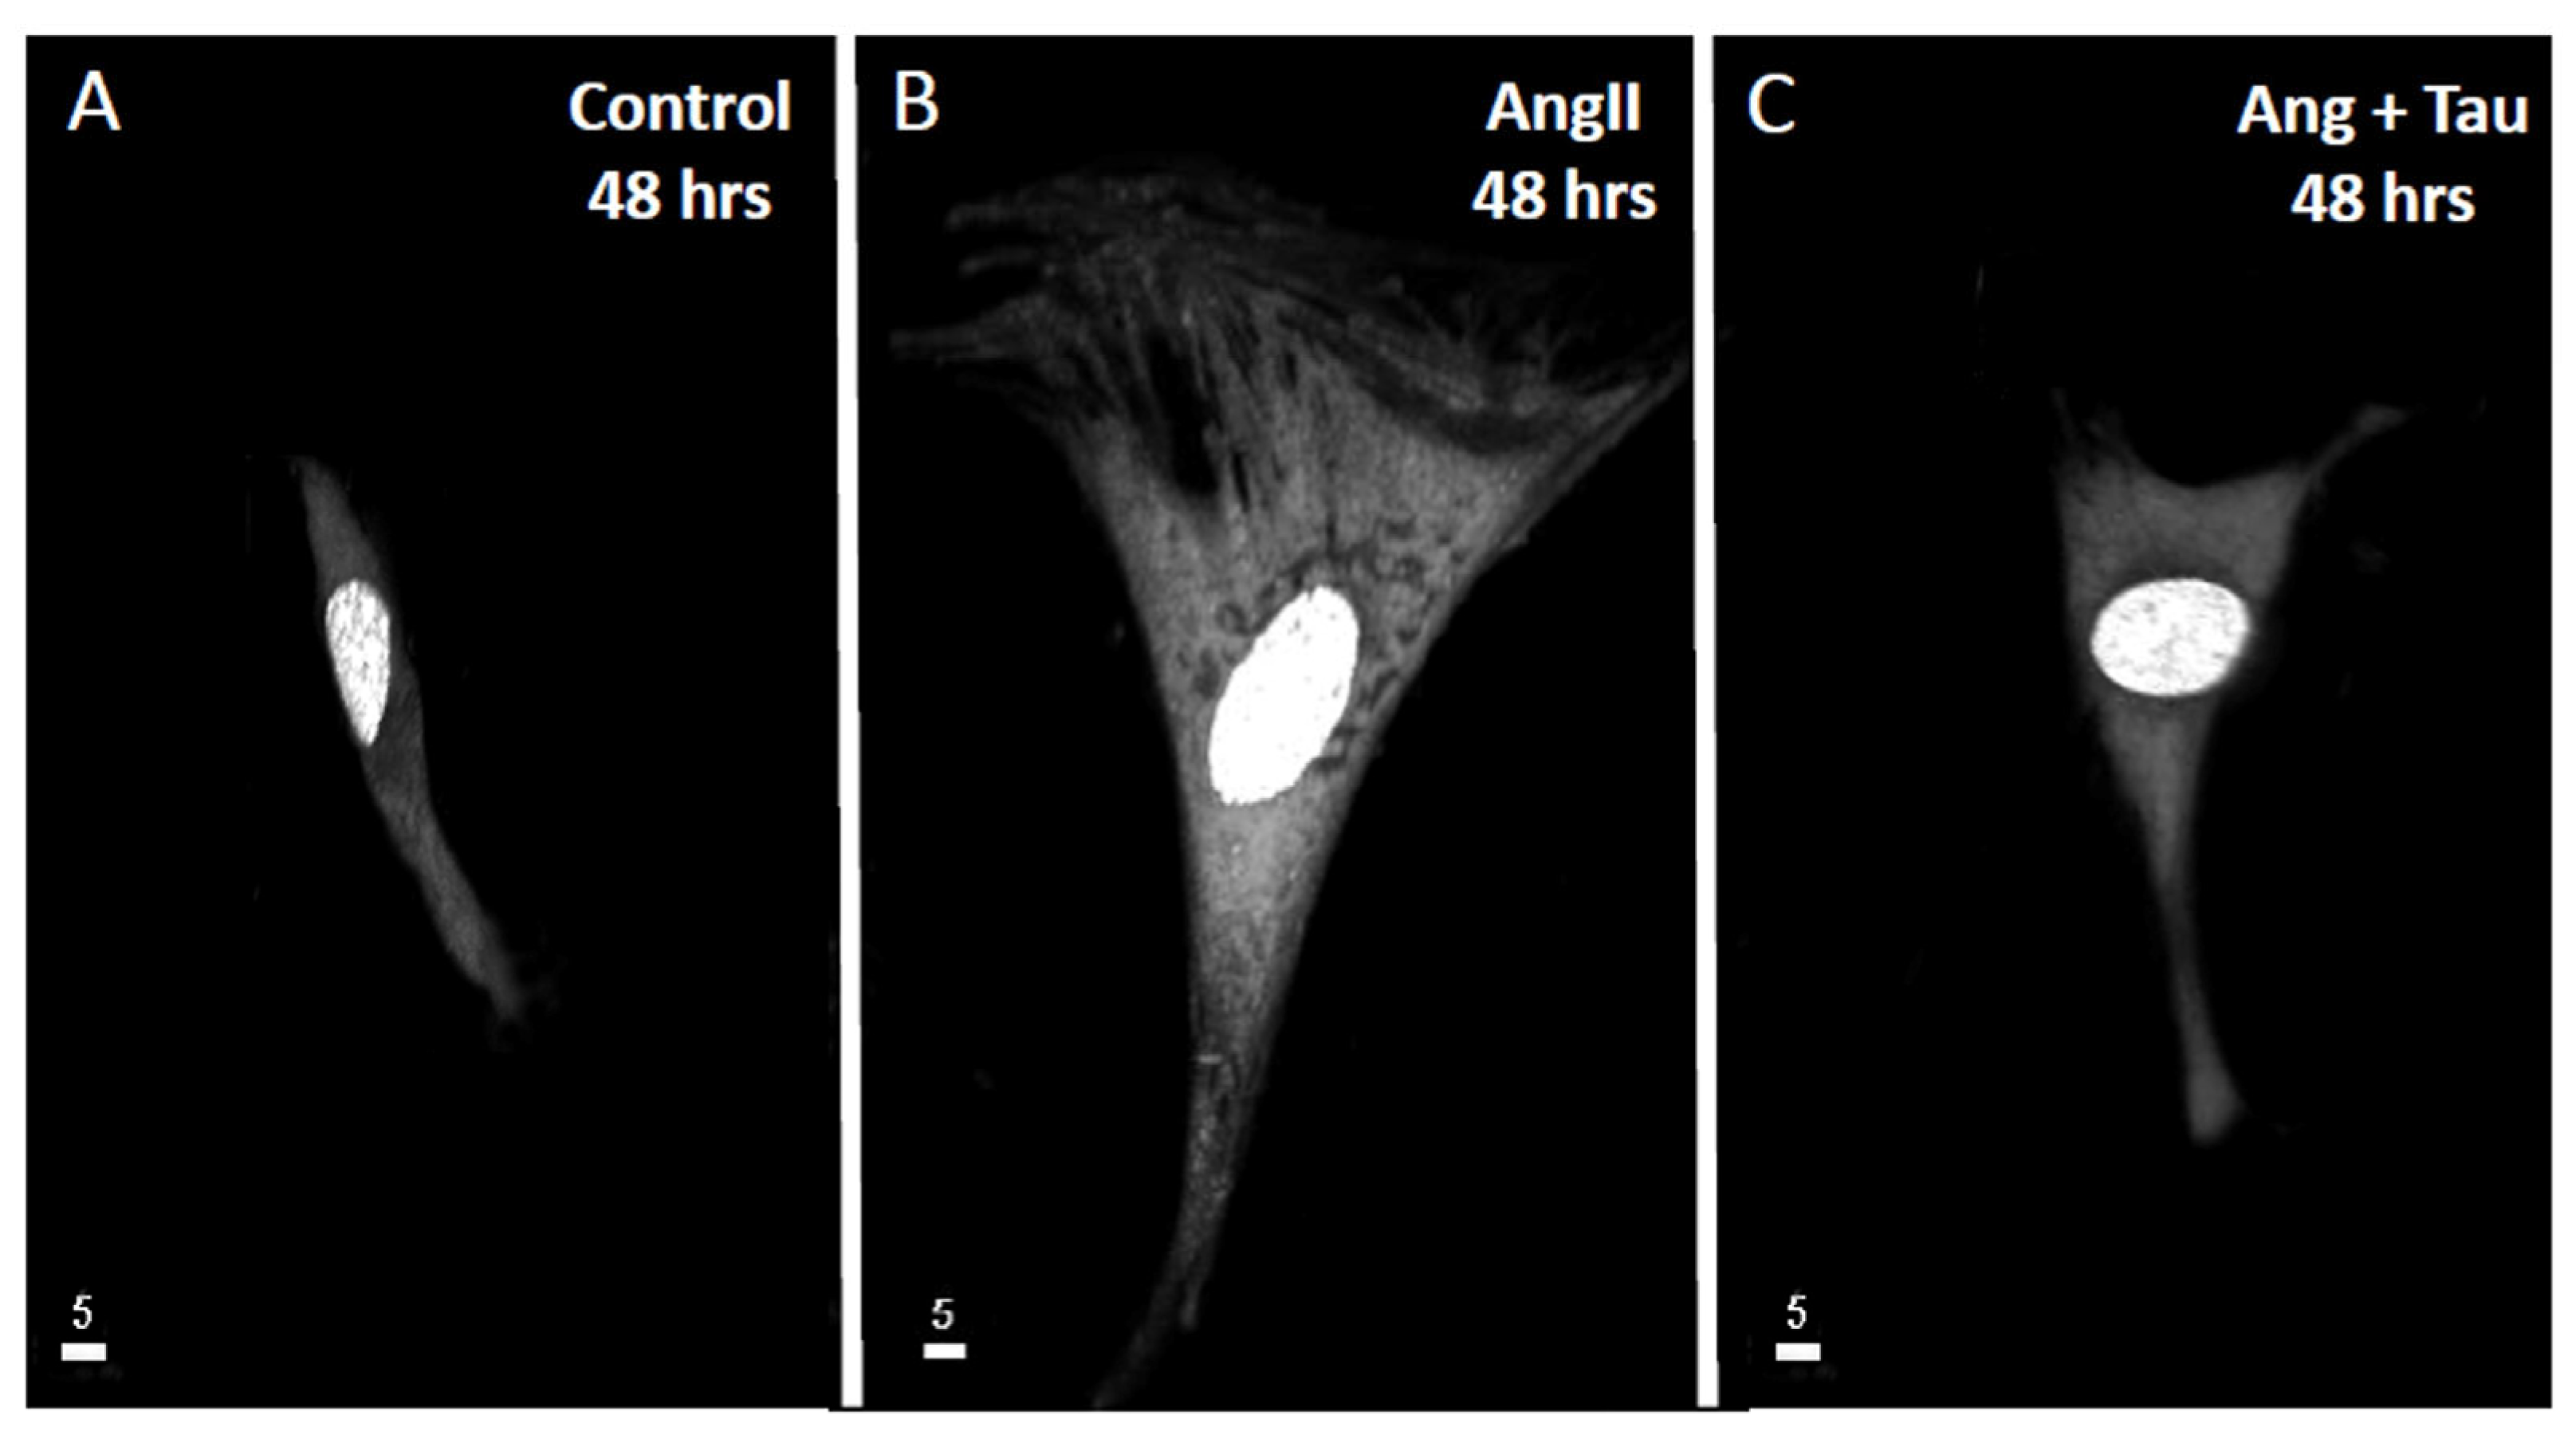

Taurine Prevents Angiotensin II-Induced Human Endocardial Endothelium Morphological Remodeling and the Increase in Cytosolic and Nuclear Calcium and ROS

Effect of Ang II on Human Ventricular Endocardial Endothelial Cells